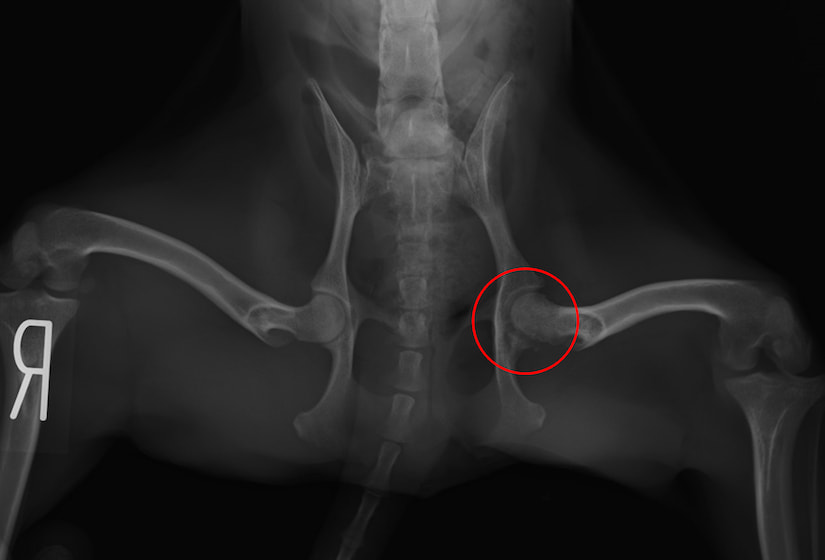

変形性脊椎症(2025/12/08)

変形性脊椎症は、身体を支えている背骨(脊椎)が年齢とともに少しずつ変形してしまう病気です。多くは無症状なためレントゲン検査で偶然見つかることも珍しくありません。しかし、変形した脊椎が神経を圧迫することで痛みや歩行異常が現れることがあります。椎間板の変性や加齢による椎体間の不安定性が原因と考えられています。症状が見られる場合は、鎮痛剤で痛みを和らげたり、温熱療法などの理学療法で筋肉の緊張をほぐしながら経過を見ていきます。最近活動量が減ってきた、歩きにくそうにしている、などの変化は病気のサインかもしれません。なにか気になる症状があればお気軽にご相談下さい。

犬の変形性脊椎症(2024/12/07)

変形性脊椎症とは身体の構造を支えている脊椎に変形が起こってしまう病気です。多くは無症状で健康診断などで偶発的に発見される事があります。しかし変形した脊椎が神経を圧迫する事でまれに痛みや運動障害を引き起こす事があります。治療は症状がある場合は鎮痛剤の投与や、温熱治療などの理学療法を行って痛みを緩和していきます。また肥満の場合には脊椎に過度な負荷をかけてしまうため、適切な体重管理が重要となります。お家のわんちゃんが高齢になって活動性が落ちてきた、歩きにくそうにしているなど気になる症状がありましたら、お気軽にご相談ください。